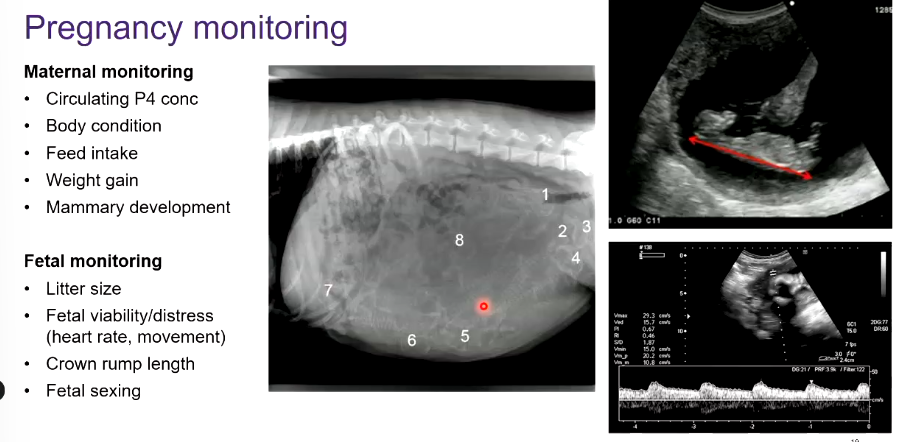

Diagnose and monitor pregnancy

A

Diagnosis:

twins - fetal reduction e.g in mares

what to monito during maternal and fetal monitoring